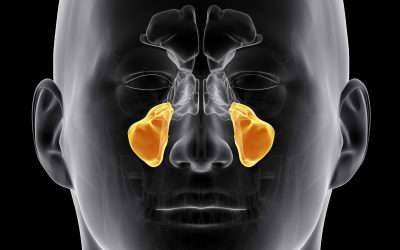

La TC Cone Beam è un’indagine radiologica tridimensionale che consente una valutazione dettagliata del cavo orale, permettendo di analizzare con precisione altezza, larghezza e spessore dell’osso, oltre alle caratteristiche anatomiche degli elementi dentali. Grazie all’elevata accuratezza diagnostica e a una dose di radiazioni inferiore rispetto alla TAC tradizionale, è ampiamente utilizzata in odontoiatria, in particolare in chirurgia orale e implantologia, per la pianificazione di interventi complessi. Le sue applicazioni si estendono anche ad altre branche come ortodonzia, endodonzia e parodontologia, rendendola uno strumento fondamentale per una diagnosi completa e personalizzata.